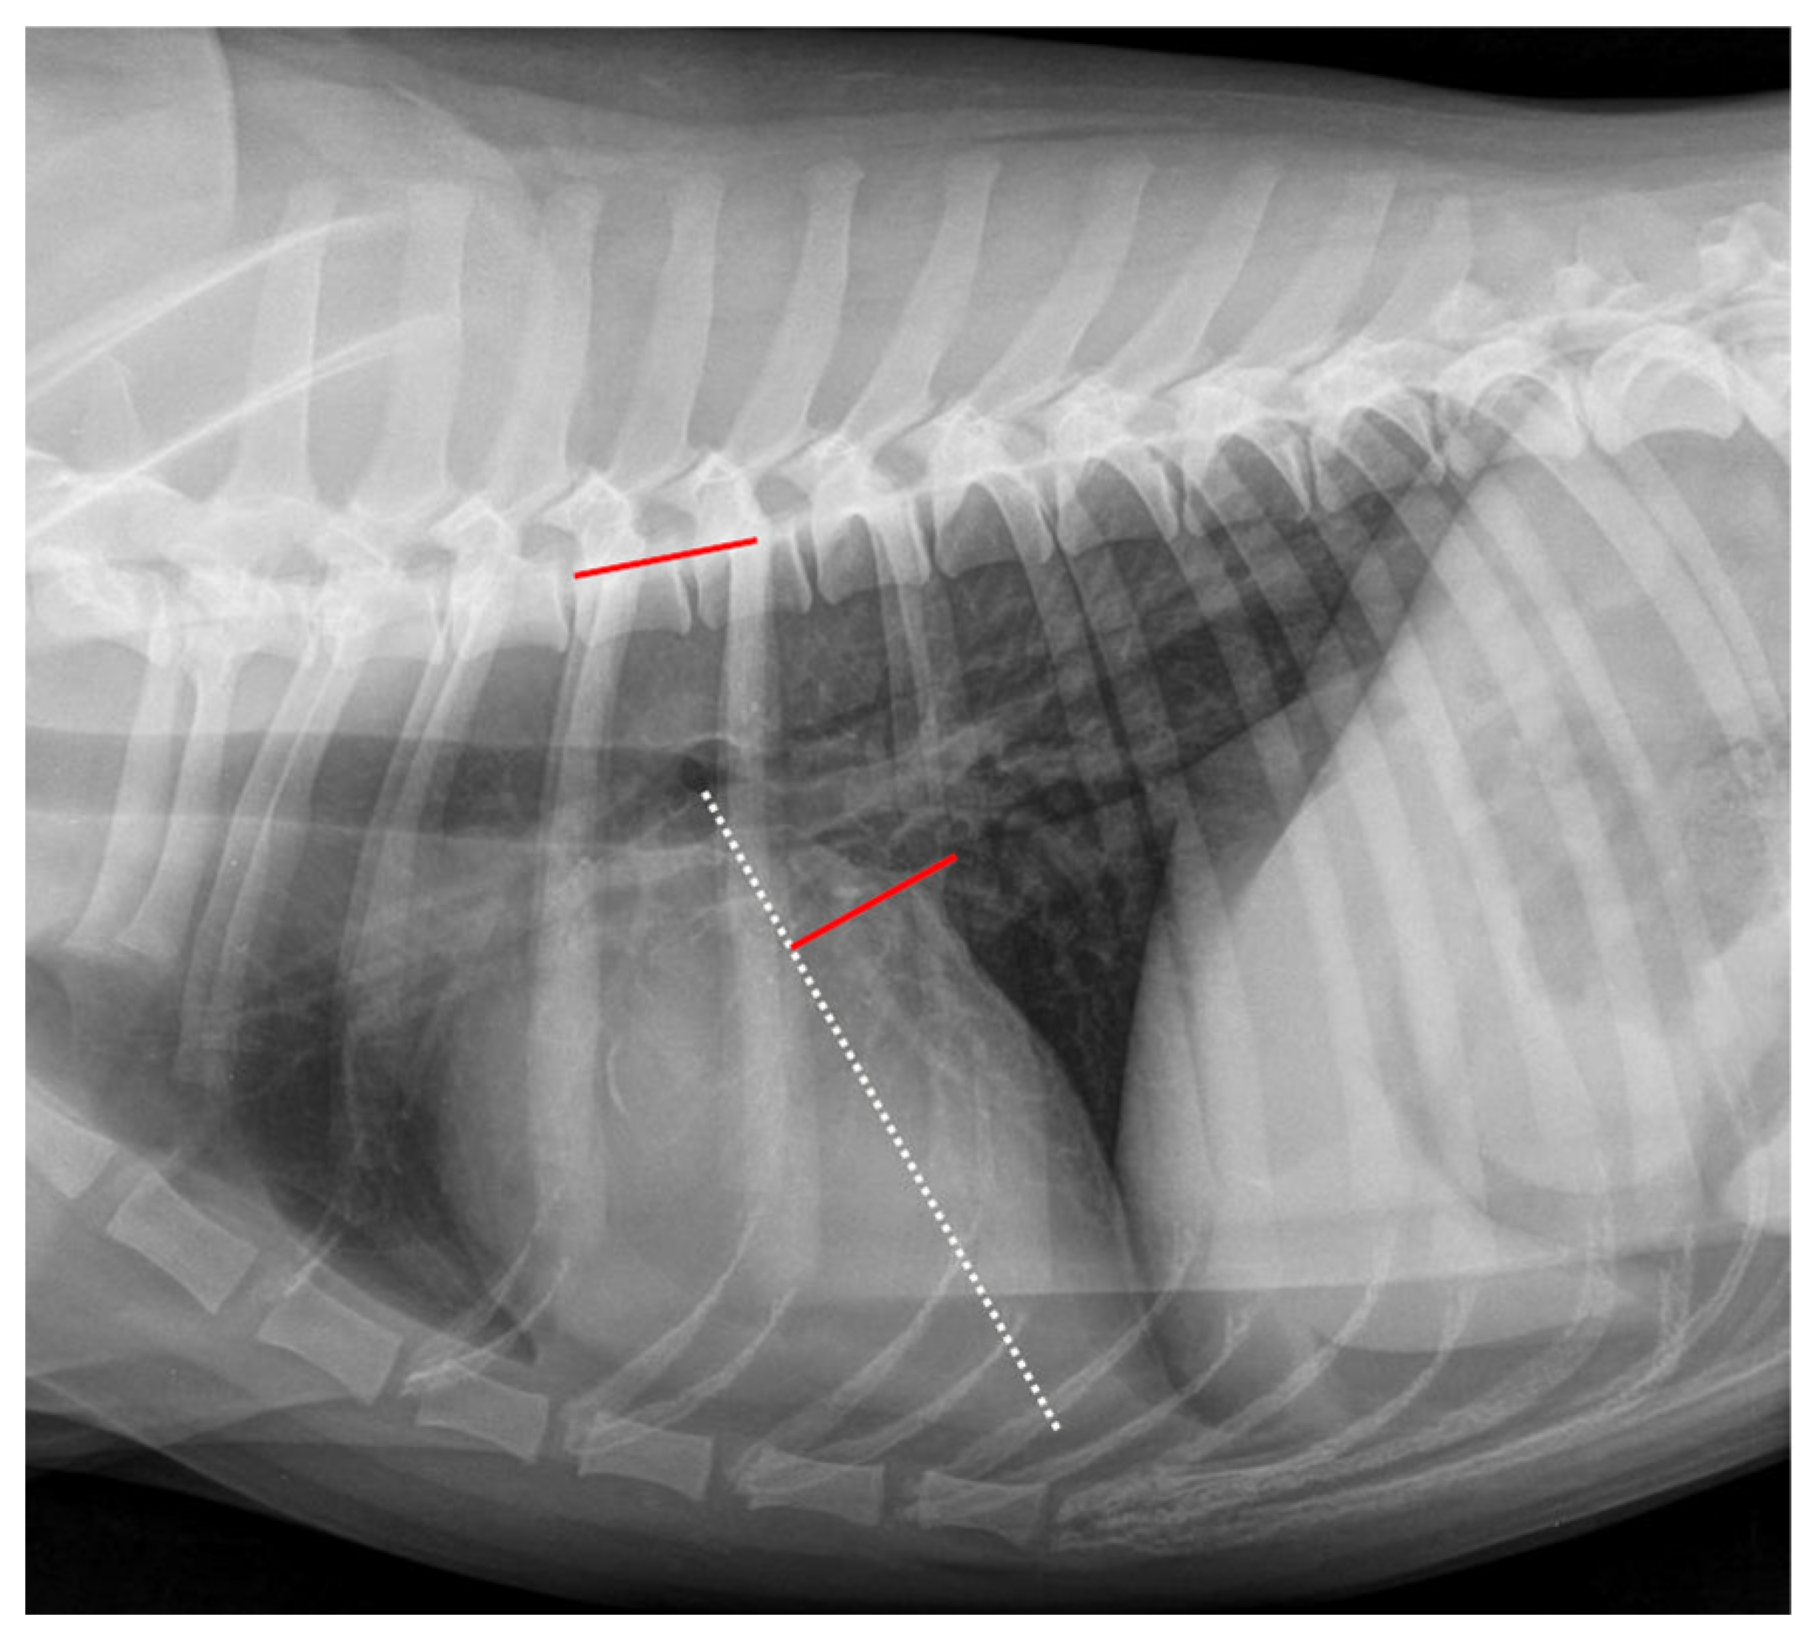

The LAWidth was measured as described by Stepien et al. (2020) [26] and is shown in Figure 3. As a basis for measuring the RLAD, two axes had to be drawn similarly as described for the VHS. The long axis was measured for VHS and RLAD. Afterward, the LAWidth line was drawn at a 90° angle at the height of the dorsal intersection between the cardiac silhouette and the caudal vena cava. This line was finally applied to the vertebral column beginning at the fourth thoracic vertebra, and the number of encompassed vertebrae was recorded as LAWidth.

Figure 3.

Measurement example of LAWidth. The Left Atrial Width (LAWidth) measurement in the same right lateral thoracic radiograph is shown in Figure 1. The long axis was measured as described in Figure 1 (white dotted line). The short axis was drawn at a 90° angle to the long axis at the height of the dorsal intersection between the cardiac silhouette and the caudal vena cava (red line on cardiac silhouette). This line was repositioned onto the vertebral column (red line on vertebral) as described in Figure 1. The LAWidth was 1.6 vertebral units.